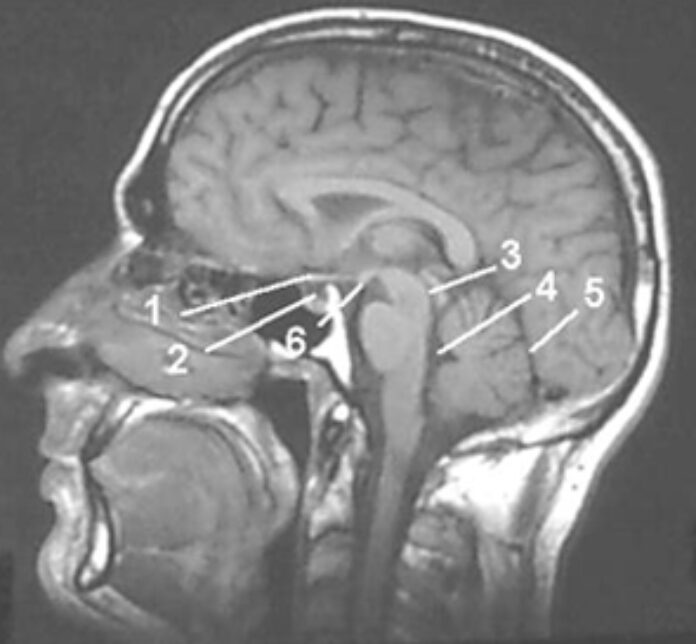

“Not only are we going to check every passenger for hidden weapons and the size of their private parts, but we will also check passengers for anomalies inside their bodies. This can only benefit the passengers, for example if we see a tumour in your rectum or lungs, we will tell you before you get on the flight about it,” Dr McKaskill told the Times.

The cash strapped NHS says that the new airport full body scanners could save the health service millions and decrease waiting times.

“If you need an x-ray on the NHS, or an MRI body scan, the waiting list can sometimes be weeks or months. The airport full body scanners will save us a lot of money on everyone who travels plus decrease waiting times for patients,” an NHS spokesman said.